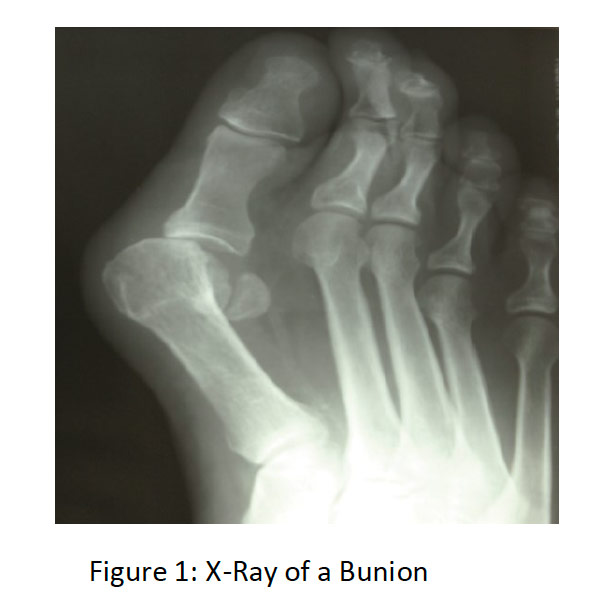

Xray Showing Bunion On Human Foot Photo Getty Images